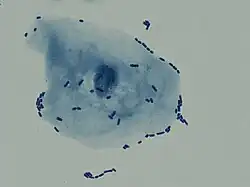

| Multiple white cells seen in the urine of a person with a urinary tract infection using microscopy | |

In straightforward cases, a diagnosis may be made and treatment given based on symptoms alone without further laboratory confirmation.[4] In complicated or questionable cases, it may be useful to confirm the diagnosis via urinalysis, looking for the presence of urinary nitrites, white blood cells (leukocytes), or leukocyte esterase.[54] Another test, urine microscopy, looks for the presence of red blood cells, white blood cells, or bacteria. Urine culture is deemed positive if it shows a bacterial colony count of greater than or equal to 103 colony-forming units per mL of a typical urinary tract organism. Antibiotic sensitivity can also be tested with these cultures, making them useful in the selection of antibiotic treatment. However, women with negative cultures may still improve with antibiotic treatment.[4] As symptoms can be vague and without reliable tests for urinary tract infections, diagnosis can be difficult in the elderly.[11]